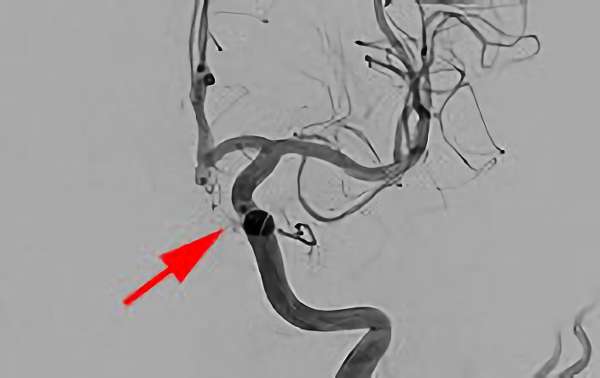

No.1631 手術前